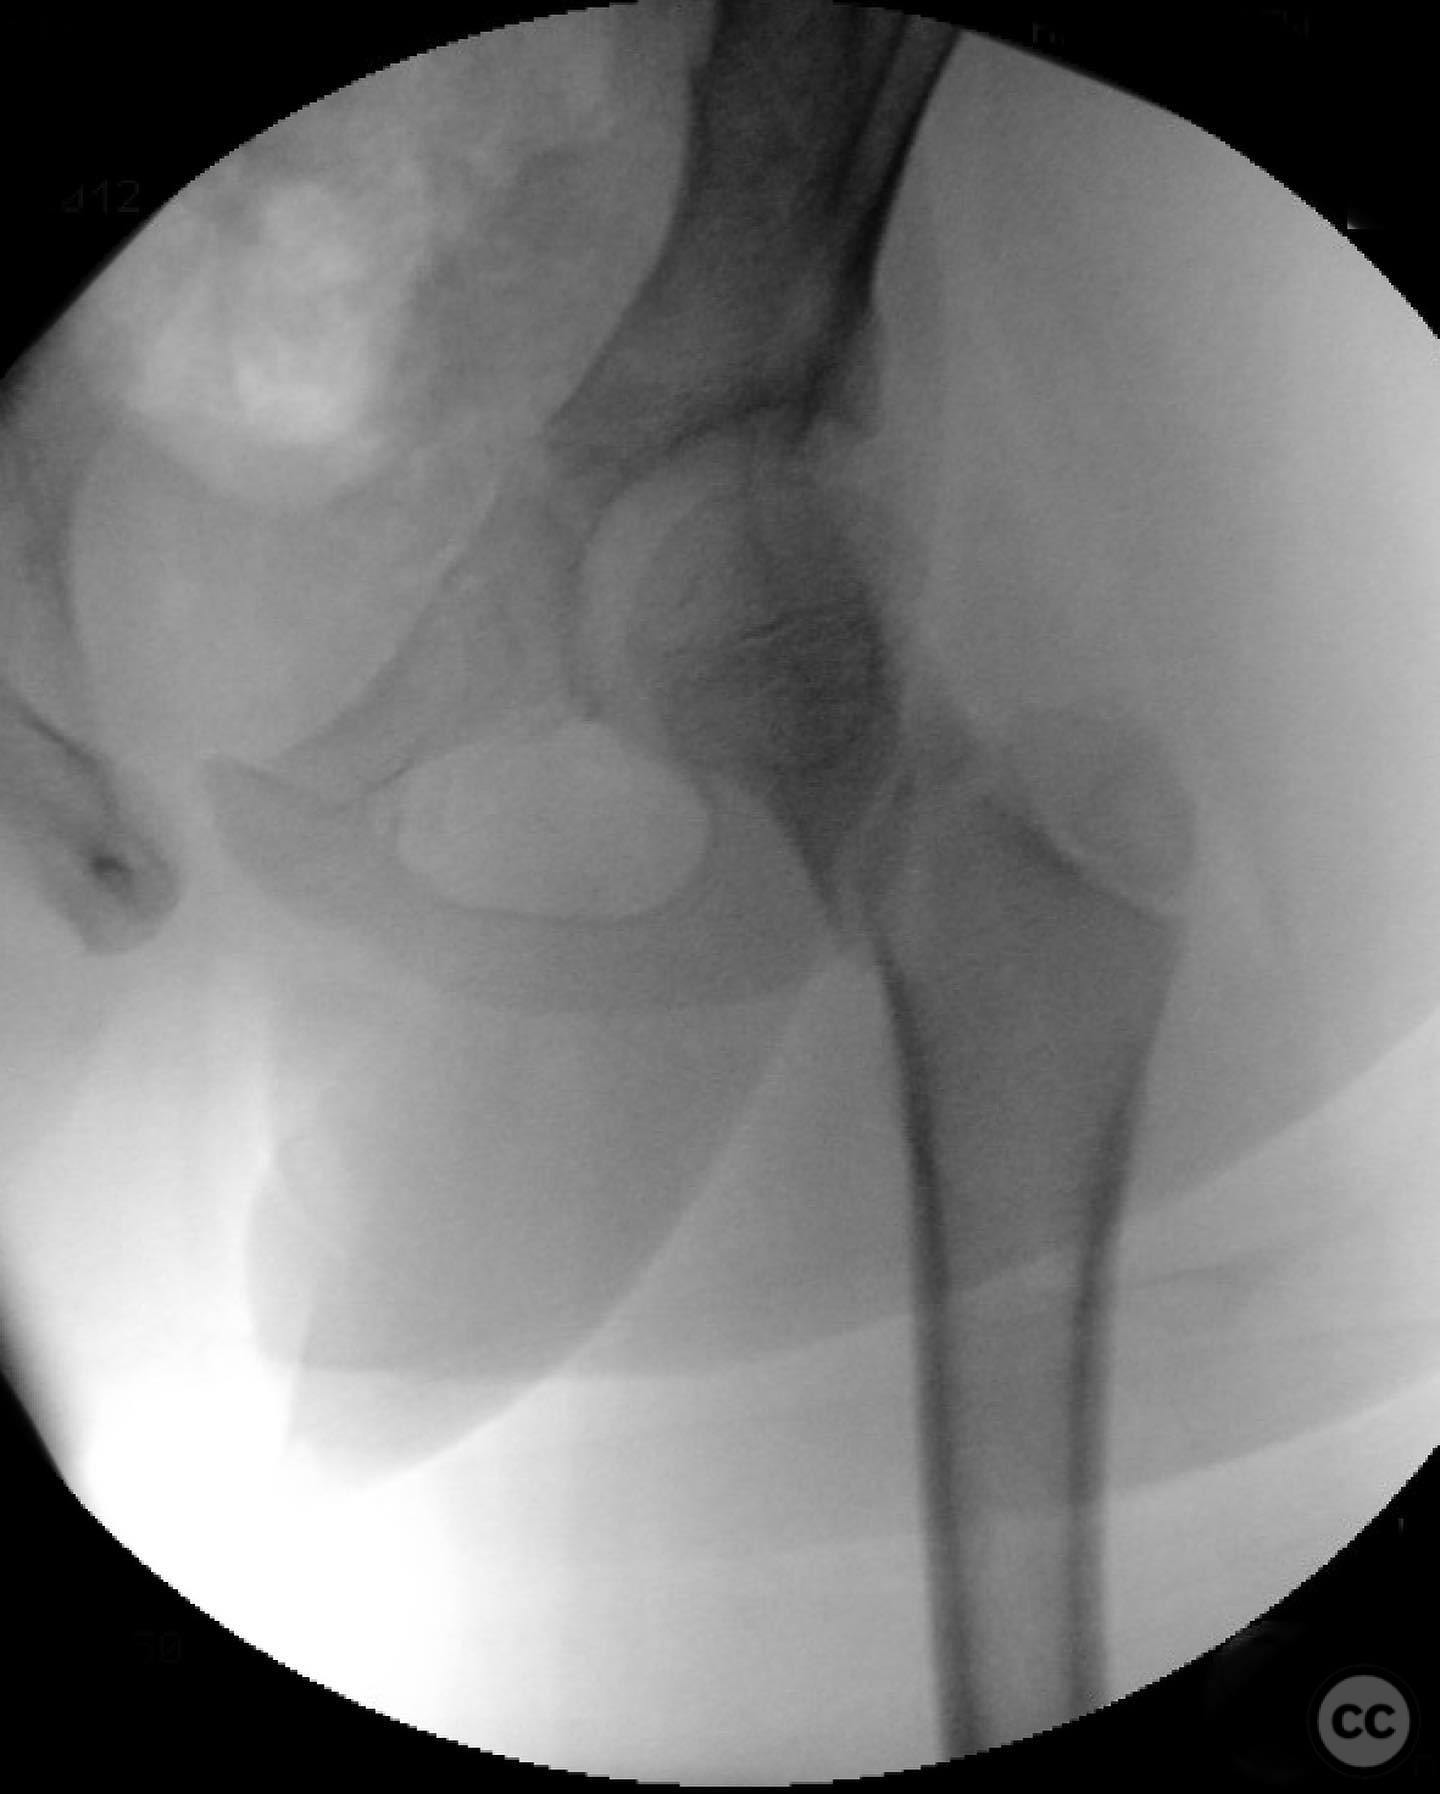

Clinical and radiological findings:  An 8-year-old boy fell approximately 15 feet from a treehouse, sustaining a displaced femoral neck fracture. There were no associated injuries to the head, spine, chest, or abdomen. The initial radiological assessment confirmed a displaced fracture of the femoral neck. Neurovascular examination was unremarkable.

Patient positioning:  Supine position on a radiolucent table to facilitate intraoperative imaging and access to the femoral neck.

Anatomical surgical approach:  A modified Smith-Petersen approach was utilized, involving an incision along the anterior aspect of the hip, allowing for direct visualization of the femoral neck. Subperiosteal dissection was performed to expose the fracture site without compromising the surrounding musculature. A separate lateral approach was employed for the application of fixation devices.